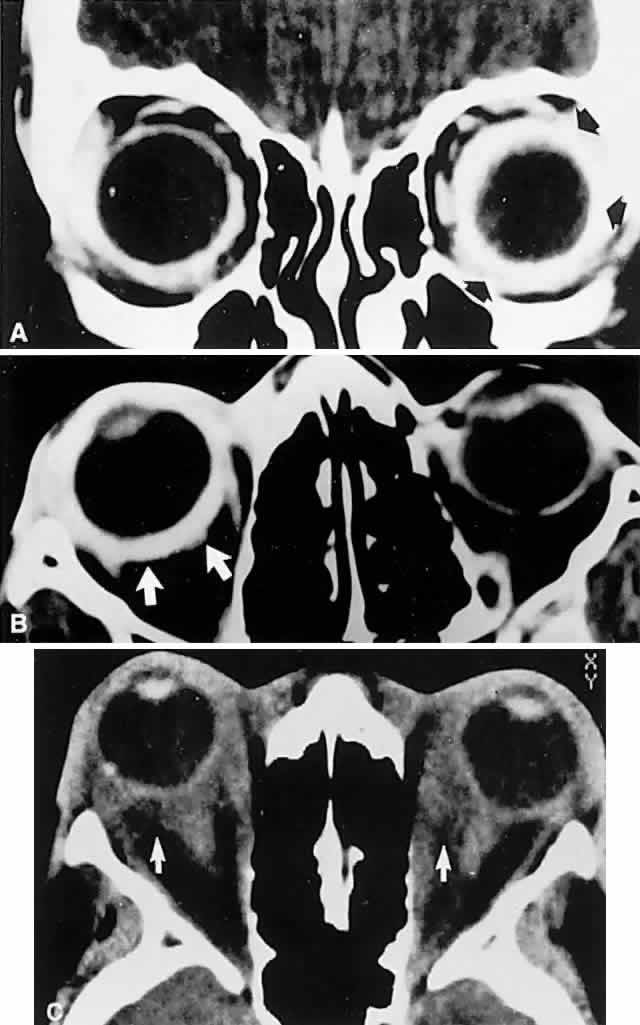

Orbital inflammatory disease may take several distinct forms. Acute orbital cellulitis is defined as infectious inflammation of soft tissues posterior to the orbital septum, characterized by distension and hyperemia of the lids and conjunctiva, pain, proptosis, and limitation of eye movements. Although sinus infections were formerly frequently associated, this is now a relatively rare condition, thanks to the availability of antibiotics. However, the condition is potentially life-threatening. Principal predisposing risk factors include ocular or adnexal surgical procedures (lid, strabismus, or retinal operations), facial or orbital trauma, especially with retained orbital foreign bodies, dacryocystitis or other periorbital infections, insect bite envenomization, diabetes, and immunosuppressive states. Especially in children and young adults, orbital cellulitis is still associated with ethmoidal and maxillary sinusitis. Those bacterial agents commonly responsible for sinusitis (predominantly Streptococcus pneumoniae, Staphylococcus aureus, and less frequently Haemophilus influenzae), not surprisingly are implicated in orbital cellulitis.41 Rapidly progressive rhabdomyosarcoma may present a clinical picture of pseudocellulitis in children (see Fig. 3). CT scanning or MRI is mandatory, not only to disclose sinus disease, but also to determine the presence of meningitis, cavernous sinus thrombosis, or orbital abscess formation, which requires surgical drainage. Most associated abscesses occur in the medial orbit adjacent to the ethmoidal sinuses, with spread of infection via communicating veins (septic thrombophlebitis) or across the thin lamina papyracea. Chronic mucoceles may also be associated with cellulitis or abscess formation.

Orbital pseudotumor and the Tolosa-Hunt syndrome are likely the same process, varying only in that the idiopathic inflammation involves predominantly the orbit in the former and predominantly the superior orbital fissure and/or the anterior cavernous sinus in the latter. Idiopathic inflammation is a diagnosis of exclusion, made only in a fairly circumscribed clinical context, and when other pathologic processes have been ruled out. In this regard, contrast-enhanced CT scan or MRI shows diffuse infiltration or focal lesions, usually with notable enhancement of the posterior wall of the globe (Fig. 15). With proper orbital imaging and ultrasonographic assessment as diagnostic procedures, tissue biopsy is rarely necessary, and the response to systemic corticosteroid administration is usually dramatic, if not diagnostic (see also Volume 2, Chapter 12).

Fig. 15. Contrast-enhanced computed tomography (CT) scan in patient with painful ophthalmoplegia, lid swelling, and proptosis. In unilateral case, note enhancing envelope of thickened sclera (arrows) on coronal (A) and axial (B) sections of left globe. C. Bilateral orbital pseudotumor shows shaggy infiltration of orbital soft tissues (arrows) surrounding globes and optic nerves.